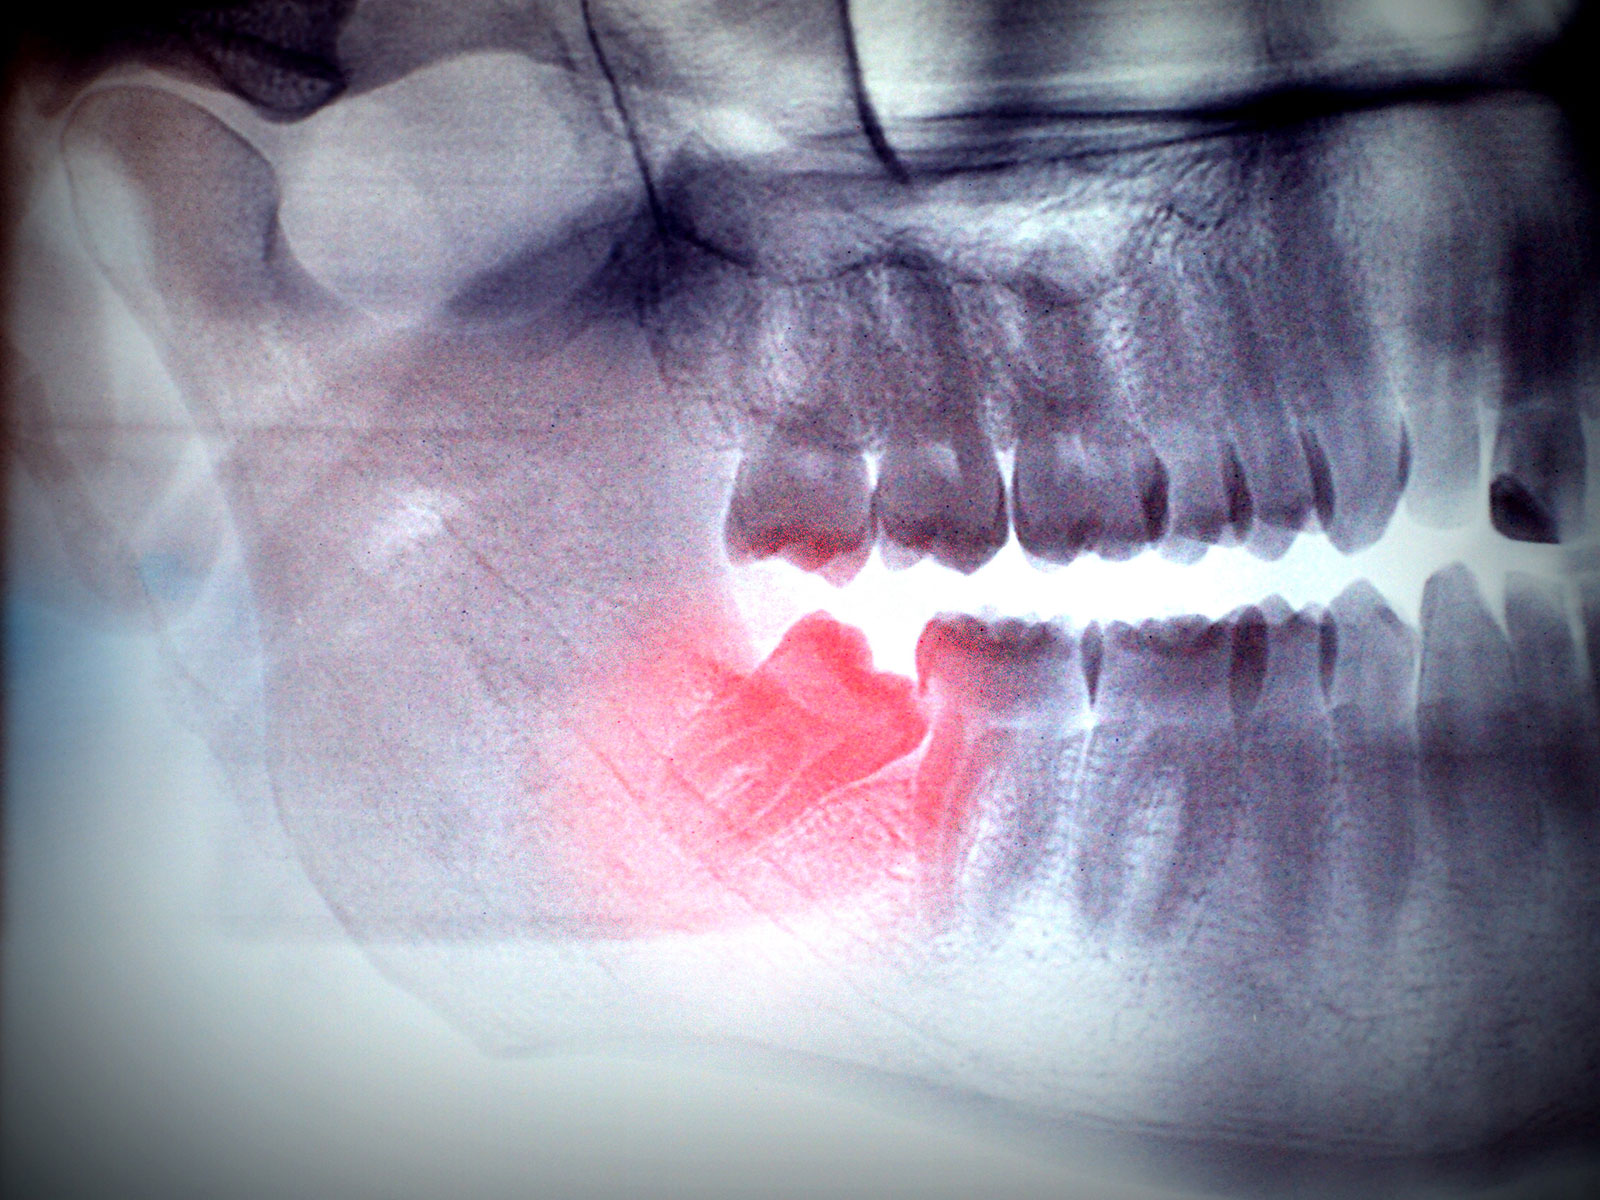

Extraction of Wisdom Teeth

The extraction of wisdom teeth is a procedure to remove one or more wisdom teeth, the four permanent adult teeth in the back corners of the top and bottom of your mouth. Most people have these teeth removed for a number of reasons including pain, discomfort, inflammation, infection or causing damage to neighboring teeth. The surgery is the removal of gum tissue that covers the tooth, detaching the connective tissue that is between the tooth and the bone and finally, removing the tooth and suturing the gum line.